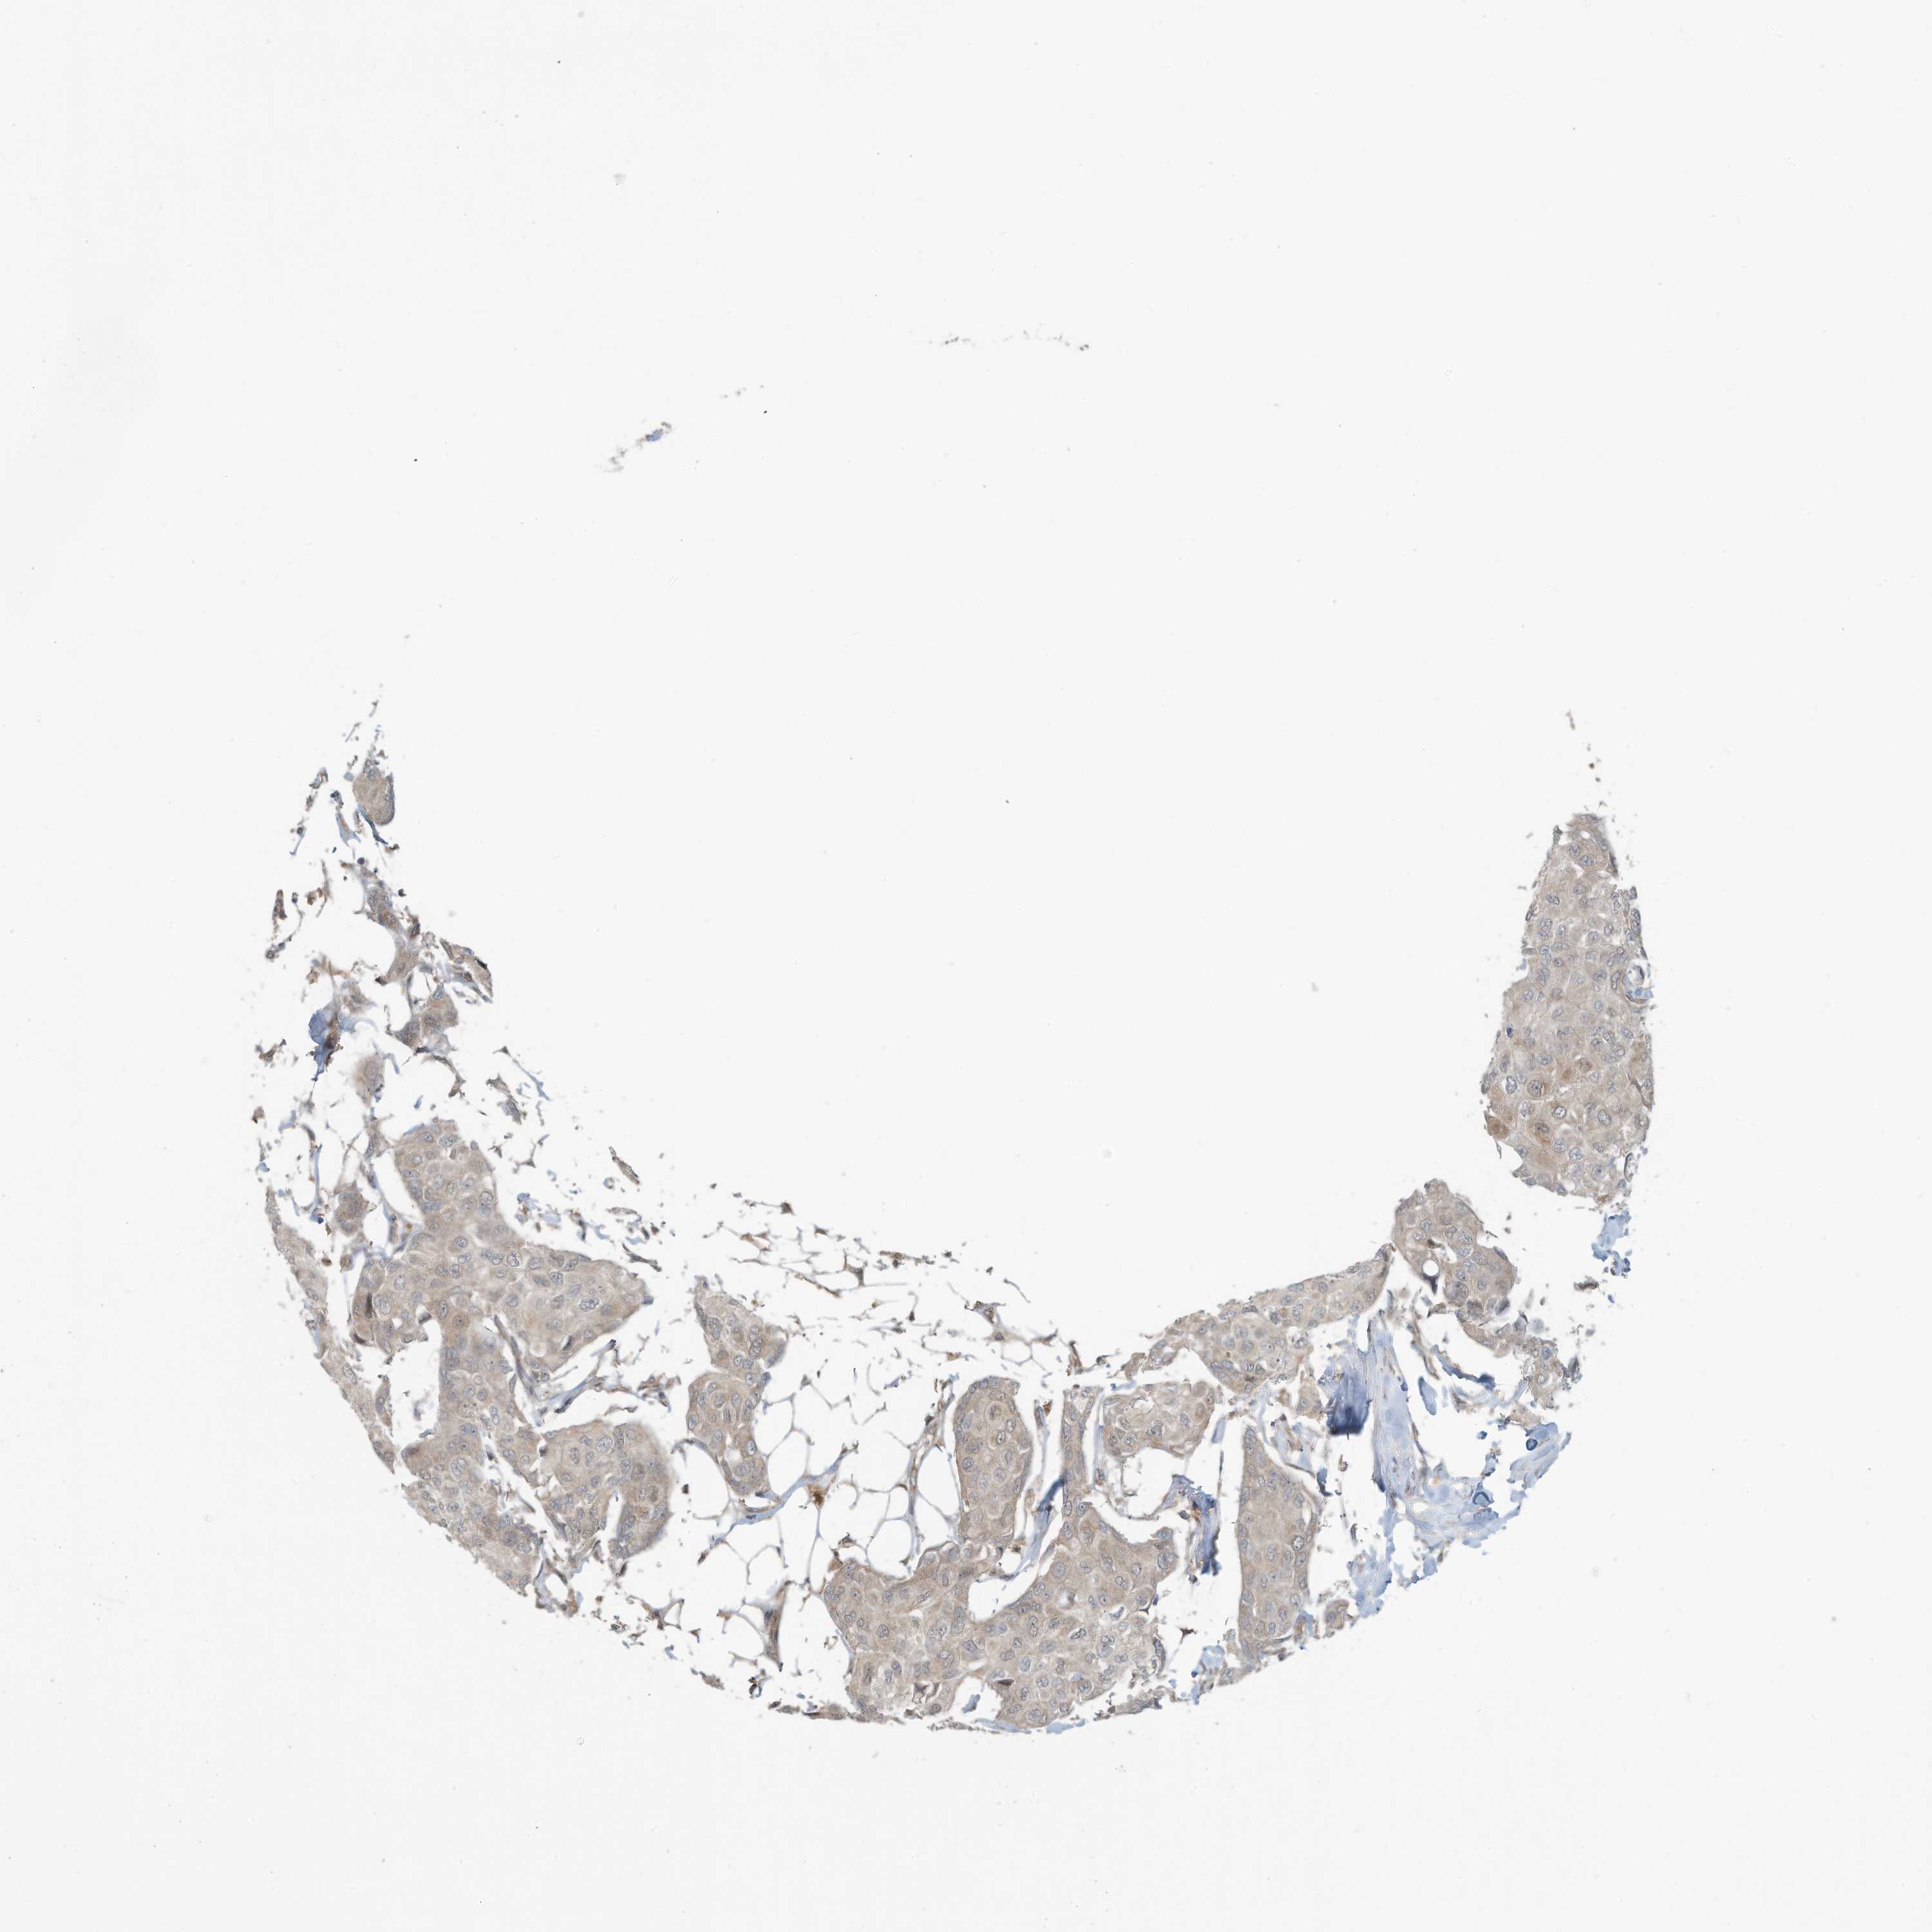

BRCA TCGA BRCA VALIDATION PROTEIN EXPRESSION

ANTIBODIES

AND

VALIDATION